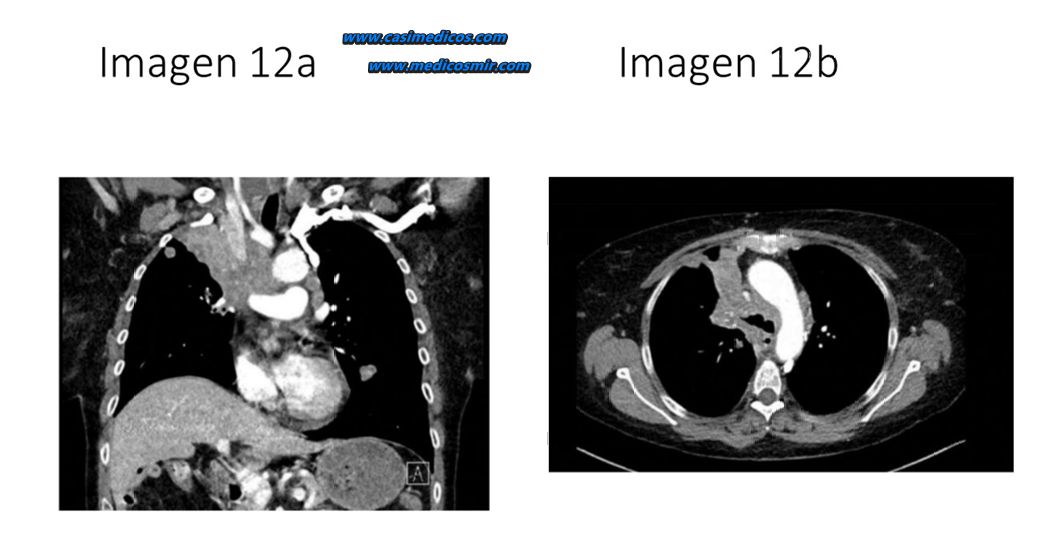

Paciente de 70 años fumador de 2 paquetes de cigarrillos al día. Acude a urgencias por disnea, plétora facial, edema en esclavina y cianosis. Se realiza una Tomografía axial computarizada (TAC) de tórax en el que se observan las siguientes imágenes (IMAGEN 12a y 12b). ¿Cuál es el diagnóstico más probable?

Comentario: TC torácica que muestra masa pulmonar en lóbulo superior derecho con infiltración mediastínica que condiciona compresión de la vena cava superior, en paciente fumador con clínica de síndrome de vena cava superior. La causa más frecuente es el carcinoma microcítico de pulmón.